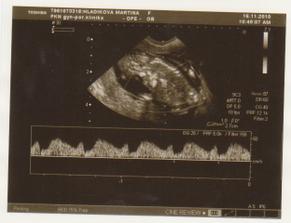

NT screening 12+4tt